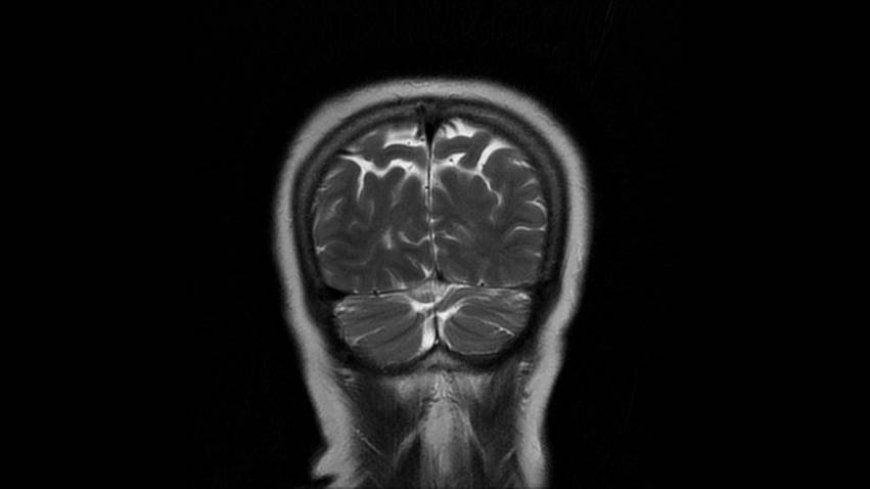

MRI of Brain

Coronal T2